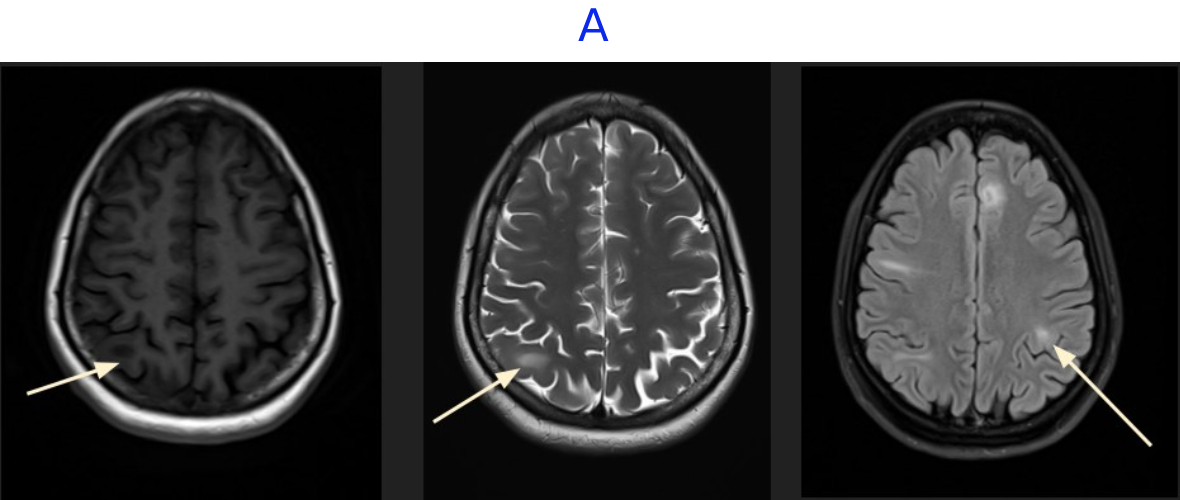

• A. MR BRAIN

• A. There are multiple cortical and subcortical lesions seen in both cerebral hemispheres, most prominently involving the frontal and parietal lobes. These lesions demonstrate T2/FLAIR hyperintensity with corresponding T1 hypointensity, without associated mass effect. No evidence of any diffusion restriction or post-contrast enhancement.